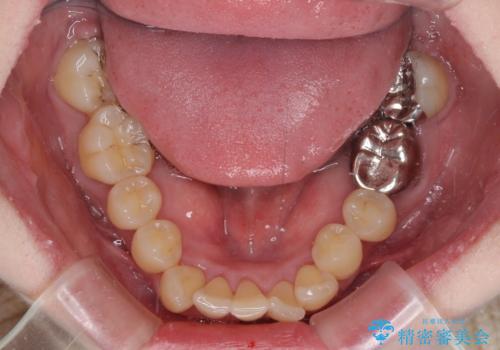

- 八重歯と正中のズレを気にして来院された患者様です。

上顎左側が八重歯になっており、上顎正中が左側にずれていました。

上顎左側の第一小臼歯を抜歯し、補助装置を用いて正中位置を改善しながら八重歯を解消していくこととしました。

下顎前歯が1本欠損していたため、上下正中の位置が合わせるという目標はなく、鼻筋に上顎正中を合わせていくように移動を行いました。